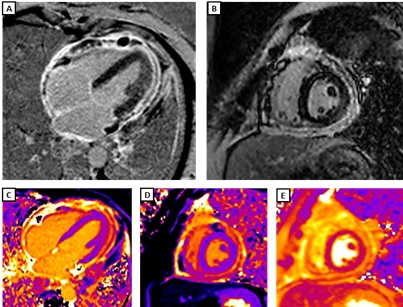

Figure 2. CMR findings at 3-month follow-up. Compared with the initial study, there is persistent pericardial enhancement on PSIR sequences 10 minutes after gadolinium infusion: A) four-chamber view and B) mid-ventricular short-axis view. Partial improvement is observed in pericardial mapping values — T1 mapping (1000 ms): C) four-chamber view and D) mid-ventricular short-axis view; T2 mapping (60 ms): E) mid-ventricular short-axis view. Findings are consistent with chronic constrictive pericarditis with residual inflammation.